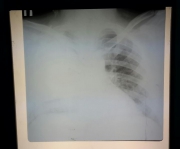

-Ой, как хорошо, что вы пришли пораньше. Мы вас так ждали, так ждали. У нас очень тяжёлый и неясный больной. Мы вот так вас ждали, что вы счас разберётесь с ним. -Да вы офигели просто! В субботу ждать дежурного врача, чтобы он разбирался ночью с больнм, который у вас весь день провёл! -Ой, ...

Часы пробили полночь. И тут прорвало конкретно. Острый отит в течении трех дней с подчелюстным лимфаденитом может заставить обратиться в больницу только в воскресенье в 0:15. Не успел оглянуться, как под дверью сидел боец с фронтов окружающей действительности. У бойца перелом челюсти и ...